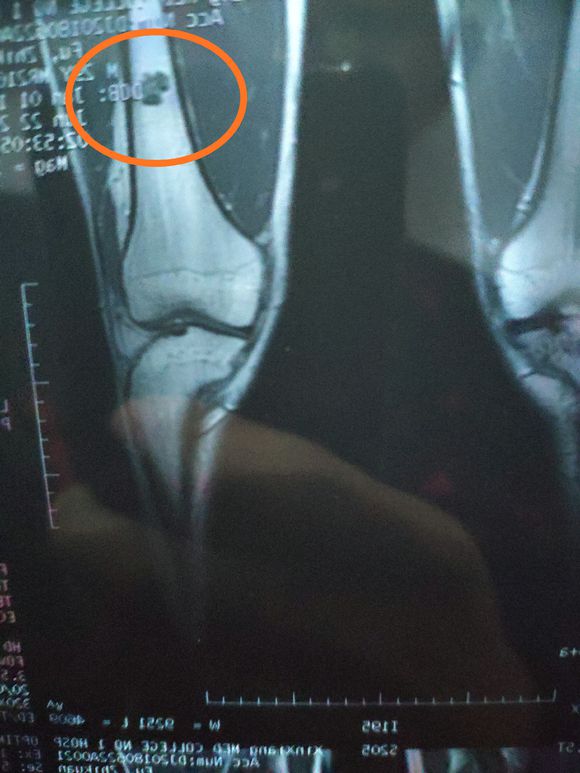

身心俱疲斗争 02019-02-22 患者家属女儿14岁,明天做截肢手术。医生让从髋关节处截,想保留个七八公分。问问大神们髋关节以下留七八公分能用常规的假肢吗? ...

一路向北 02019-01-28 患者家属我孩子今年15岁,年初查出骨肉瘤,左腿关节处,化疗5次做载肢,手术后伤口感染误了化疗,两个多月快三个月发生肺转,如今刚住...